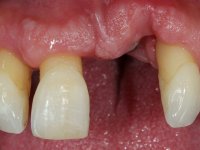

Male patient, 55 years old, smoker. Presented to our dental appointment with a dental implant placed in the area of tooth 21. The gingival architecture in the area lack interdental papilla and showed a vertical deficiency of the soft tissue. Adjacent teeth had significant root exposure.

I’ve decided to rehabilitate the dental implant by closely mimetizing the crown and the root of the adjacent teeth, as well as the gingiva close to the soft tissue deformity. Thus, the prosthetic component would integrate three parts: crown, root and gingiva.

The angulation of the dental implant did not allow for a screwed prosthesis. Thus, an anatomical abutment was used and the crown margin was milled 1mm infragingival, to allow the removal of the cement. The prosthetic component included a ceramic part emulating the crown and the root of the adjacent teeth, and a gingival part to compensate the soft tissue deficiency. Periodontal surgery to regenerate soft tissue in a vertical deficiency is complex and unpredictable, hence this prosthetic option. Although unconventional, this rehabilitation was well accepted by the patient, easy to perform and proved to be aesthetically satisfying and stable over time.